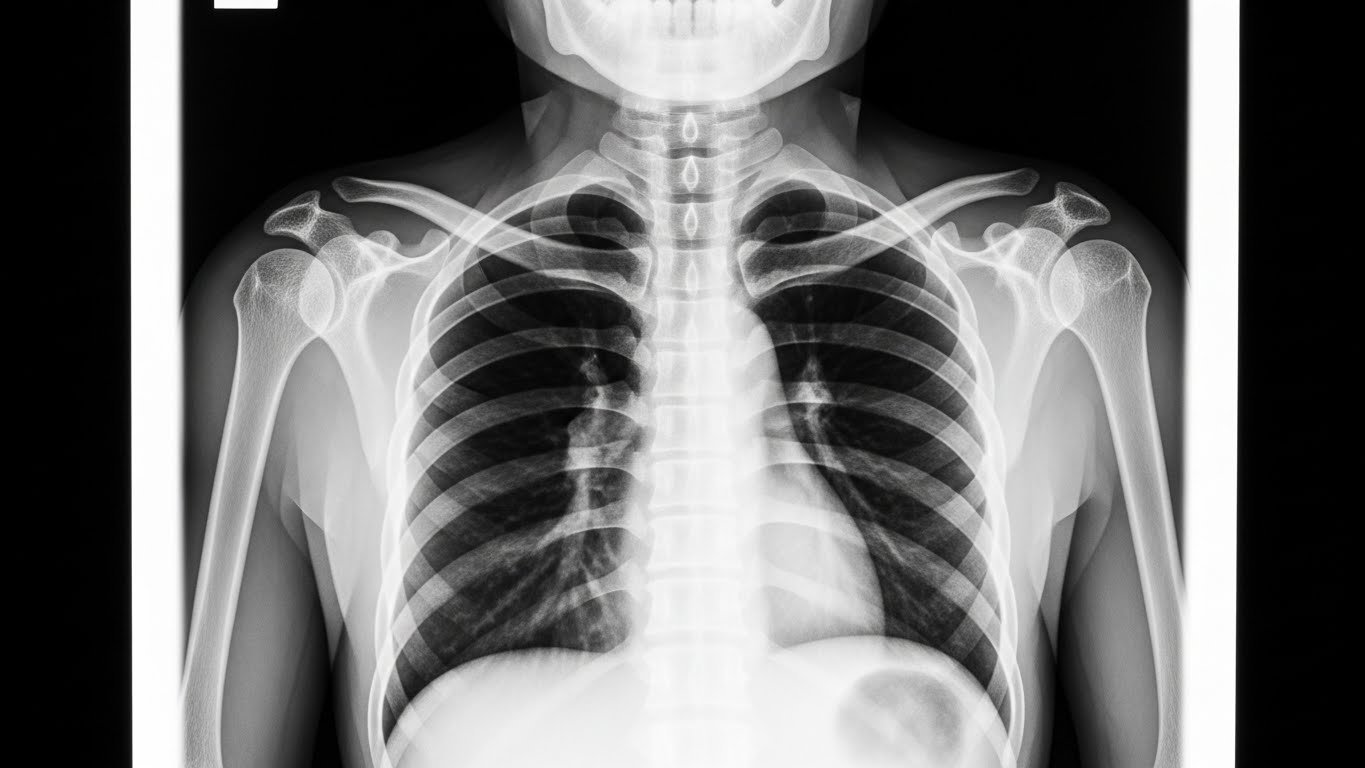

Une radiographie pédiatrique est un examen d’imagerie médicale qui utilise des rayons X pour créer des images de l’intérieur du corps de votre enfant. C’est comme prendre une « photo » qui permet au médecin de voir les os, les poumons ou d’autres organes internes.

- Radiographie du thorax : pour diagnostiquer pneumonies, bronchiolites, infections respiratoires